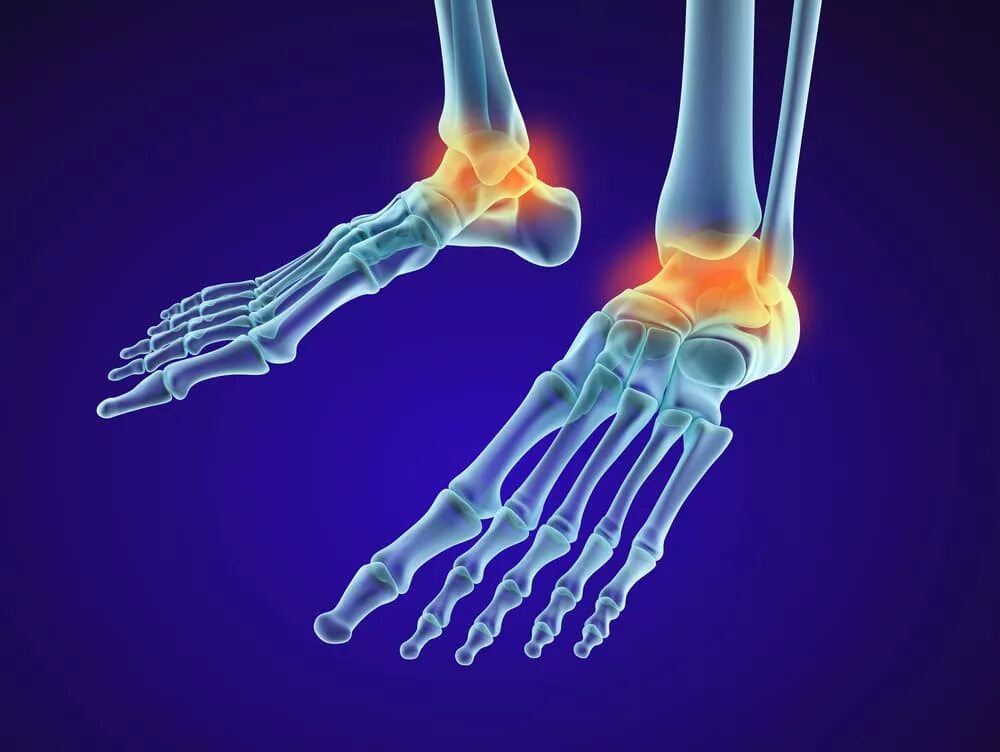

Артроз пяточных суставов